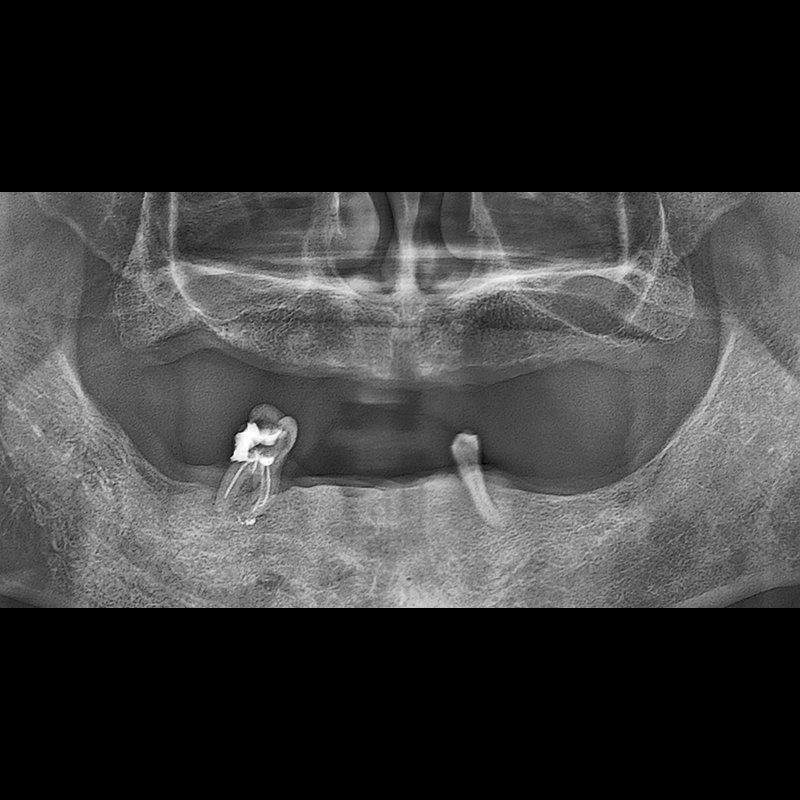

BEFORE AFTER

种植牙前后的照片 2025.05.30

在缺失的牙齿部分和难以挽救的牙齿位置植入了种植牙。